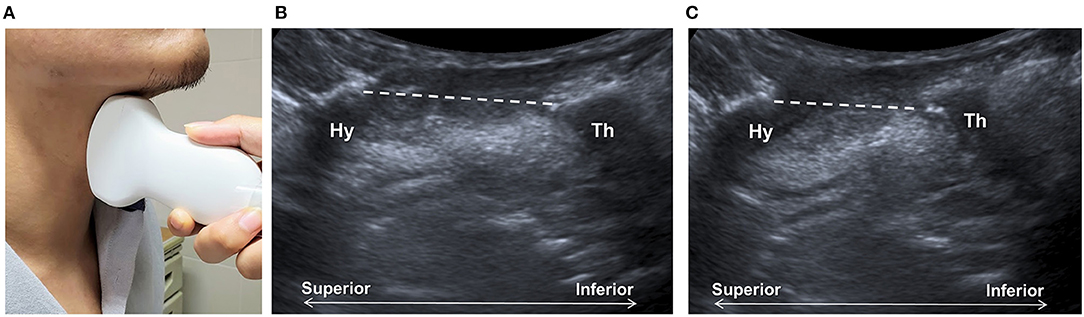

Shawker et al. (23, 24) used submental US to observe the tongue movement, raising the possibility of using this technique to observe the hyoid bone, although no reliable imaging could be obtained using a linear transducer. By placing a curvilinear transducer at the midline of the anterior neck, the approximation of hyoid bone and thyroid cartilage could be observed as a parameter to estimate larynx elevation (Figure 2) (27, 28). The measurement was found to be independent of gender and posture in another study (61). Huang et al. reported comparable results between measurements of US and VFSS and found a reduced hyoid-larynx approximation in the dysphagic stroke group (N = 40), compared with that in the non-dysphagic stroke group and the normal group (N = 15) (28). Similar findings were reported by Picelli et al. in a study of 19 patients with stroke. A correlation between the hyoid-larynx approximation and the Functional Oral Intake Scale (FOIS) was also identified (62). A recent study by Matsuo et al. reported an increased motion ratio of hyoid and thyroid displacement in patients with dysphagic stroke (N = 18) when compared with the healthy elderly (N = 18). Both sensitivity and specificity of detecting VFSS-verified dysphagia were found to be 88.9% using a motion ratio > 0.56 as the diagnostic criterion (63).

Figure 2. Ultrasonography assessment of thyroid-hyoid approximation. The transducer is placed at the midsagittal plane at the anterior neck (A), between the thyroid cartilage (Th) and the hyoid bone (Hy). Sonographic imaging demonstrates the measurement of distance (dashed line) between the thyroid bone and thyroid cartilage at the resting position (B) and at maximal approximation (C).